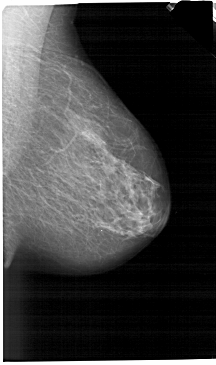

A_1455_1.LEFT_MLO

LEFT_MLO LINES 6391 PIXELS_PER_LINE 3496 BITS_PER_PIXEL 12 RESOLUTION 43.5 OVERLAY